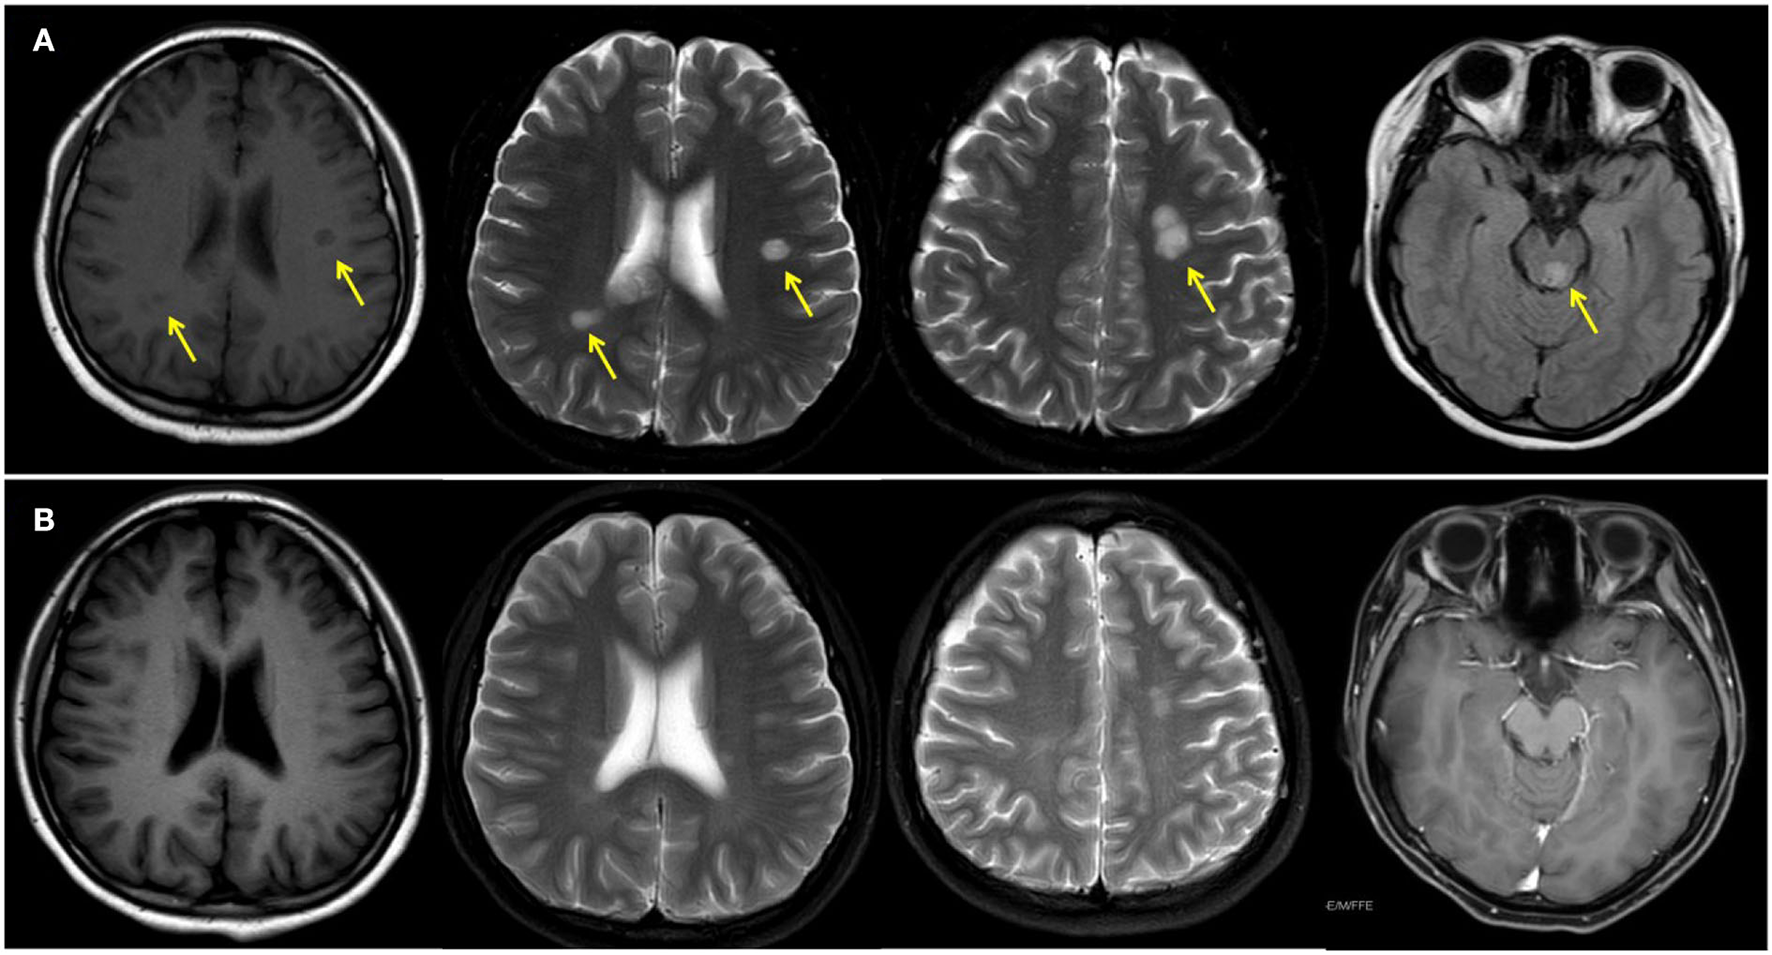

A 14-year-old girl presented with diplopia, left eyelid ptosis, right facial numbness, and right lower limb weakness since 1 month prior, which had progressively worsened. Physical examination revealed an impaired vision of both eyes, diplopia, left eyelid ptosis, right facial paresthesia, and hyperreflexia of both sides. There were no meningeal signs and no cervical, axillary, or inguinal lymphadenopathy. Routine blood tests, including blood cell counts, albumin level, transaminases, and C-reactive protein, were not significant. Brain MRI revealed multiple coin-like white matter lesions and one mesencephalon lesion (Figure 1A). Sagittal T2-weighted imaging of the brainstem and the spinal cord showed an enhanced lesion in the cerebral peduncle (Figure 2A) and in the spinal cord at the level of thoracic 12 (Figure 2B). Cerebral spinal fluid analysis showed leukocytes within the normal range, glucose was 6.25 mmol/L, albumin was 0.128 g/L, total Ig was 0.0563 g/L, IgG synthesis rate was 0 mg/day, and there were no detectable oligoclonal bands. The visual evoked potential (VEP) test was normal. She had a history of bilateral lacrimal gland enlargement about 6 months before, and a surgery was performed to correct this. Histological examination indicated lymphoproliferative changes, and the number of IgG4+ cells was over 220/HPF. Serum IgG4 was elevated (3.45 g/L, normal range 0.049–1.35 g/L). The patient was diagnosed as “IgG4-RD” and received oral glucocorticoid combined with cyclosporin but stopped 3 months later. The patient's family history was not remarkable. Based on the symptoms and MRI findings, the patient was suspected of MS and was given prednisone and intravenous immunogloblin (IVIG). Her diplopia and ptosis improved significantly and was discharged. One month later, she was administered 1 g of methylprednisolone for 5 days, followed by 70 mg of prednisone daily since her abnormal gait and lower limb weakness persisted. The prednisone was tapered to stop while recombinant interferon (IFN) β-1b was given every 2 days subcutaneously for 6 months. She did not receive any treatment for over 1 year until the development of enlargement of lymph nodes in the submaxillary and inguinal areas. Fourteen milligrams of Teriflunomide was given daily; however, her symptoms persisted. Six months later, the patient came to our department with lymph node enlargement and right-side numbness and weakness, but she denied any fever, unintentional weight loss, fatigue, or change in appetite. Laboratory tests revealed normal counts of leukocytes and platelets, the hemoglobin level, the albumin level, the serum creatinine level, and C-reactive protein. Antinuclear antibodies, extractable nuclear antigen antibodies, anti-neutrophil cytoplasmic antibodies, and anti-phospholipid antibodies were all negative. Serum IgG was 70.7 g/L (normal range 8.0–15.5 g/L), IgG4 was 28.5 g/L, and IgE was 4,810 mg/L (normal range 5–150 mg/L), while IgA and IgM were within the normal range (Figure 3). Chest computerized tomography and abdominal ultrasonography were not significant. A biopsy of the left inguinal lymph node was performed. The histopathological evaluation of the biopsy specimen of the inguinal lymph node revealed mixed inflammation containing predominantly plasma cells (Figures 4A–C). No granuloma, prominent necrosis, “onion skin pattern” mantle zones, or “lollipop lesions” were found. Immunostaining showed an increased number of IgG4+ plasma cells (>200/HPF) and an elevated ratio of IgG4+ cells to CD138+ plasma cells (~80%) (Figures 4B,C). No mycobacteria, fungi, or parasites were noticed, and Epstein-Barr virus-encoded RNA 1/2 was negative. These findings were suggestive of an IgG4-RD involving the lacrimal glands, the brain parenchyma spinal cord, and the lymph nodes according to both the ACR/EULAR classification criteria (5) and the revised comprehensive criteria (6). She had a good response to oral prednisone 40 mg daily combined with mycophenolate mofetil 750 mg two times daily. In a consecutive 7-month follow-up, her lymphadenopathy and right-side numbness and weakness resolved. A repeated brain MRI revealed shrinkage of the intracranial lesions, and the lab tests showed a rapid drop in serum levels of IgG and IgG4 (Figures 1B, 3).

Figure 1. Magnetic resonance imaging of the brain before (A) and after (B) treatment. Yellow arrows indicate white matter lesions.

Neural symptoms and white matter plaques on MRI of this patient (Figure 1) usually prompt people to consider MS. MS attacks myelinated axons in the CNS, causing progressive neurological deterioration (11). This disorder usually presents in adults between the age of 20 and 45 years with female predominance (11). Its clinical symptoms are non-specific and usually include visual changes, numbness, weakness, and paralysis, depending on the amount and area of nerve damage. MS is usually diagnosed by demonstrating clinical and/or radiographic evidence of dissemination of disease in time and space (12). This disease is characterized by elliptical or ovoid lesions found in the white matter of the periventricular and juxtacortical regions, the cerebellar peduncles, the superficial pons, and the floor of the fourth ventricles (13). Spinal cord lesions are also commonly seen. T2-weighted imaging of the spinal cord demonstrates small and circumscribed high-signal lesions that are aligned with the long axis of the cord. The lesions are usually less than two vertebral segments in length and involve less than half the axial cord area (13). In this patient, MRI revealed multiple ovoid lesions in the white matter and mesencephalon, and an enhanced lesion in the spinal cord at the level of thoracic 12, which are similar to MS lesions. Because cerebral IgG4-RD and MS have distinct outcomes, distinguishing between these two entities is critical. However, clinical judgment is often required to make the classification given an absence of specific biomarkers and clear diagnostic criteria.